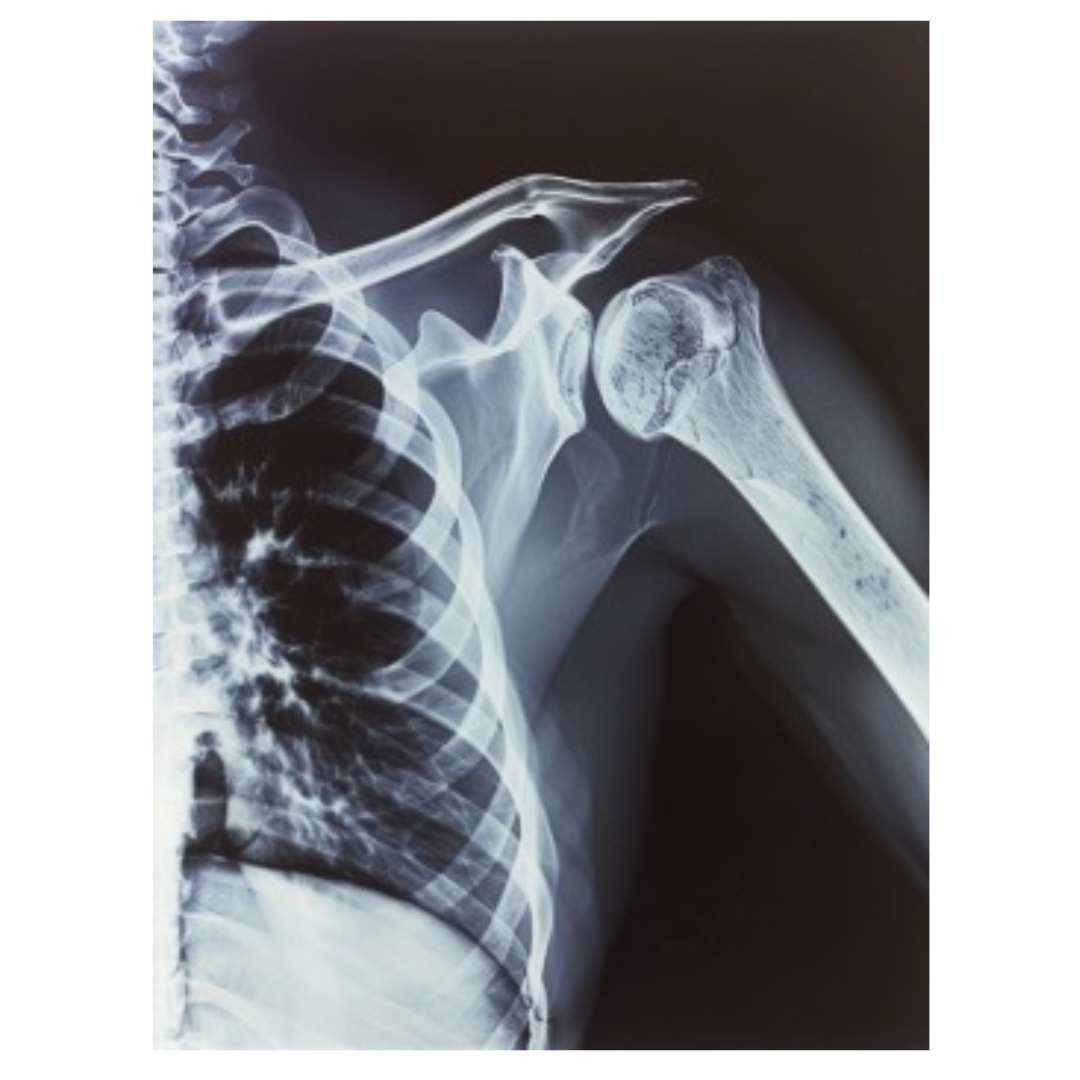

4. 어깨통증 원인 - 어깨 탈구 (Shoulder Dislocation)

어깨 탈구는 어깨 관절이 원래 위치에서 벗어나는 상태를 말합니다. 탈구가 발생하면 어깨를 움직이기가 매우 힘들어지고, 탈구가 자주 반복되면 만성 통증으로 이어질 수 있습니다.

어깨는 구조상 탈구가 비교적 쉽게 발생하는 관절 중 하나로, 스포츠 활동 중에 많이 나타나죠. 탈구가 일어나면 즉시 응급 처치가 필요합니다.

5. 어깨통증 원인 - 쇄골 골절 (Clavicle Fracture)

쇄골, 즉 어깨뼈가 골절되면 어깨 통증은 물론, 팔을 움직이기가 매우 힘들어집니다. 이 골절은 교통사고나 낙상과 같은 충격으로 인해 발생하는 경우가 많습니다.

특히 쇄골은 어깨의 움직임에 중요한 역할을 하기 때문에 골절이 발생하면 즉시 치료가 필요하며, 회복 후에도 재활이 중요합니다.